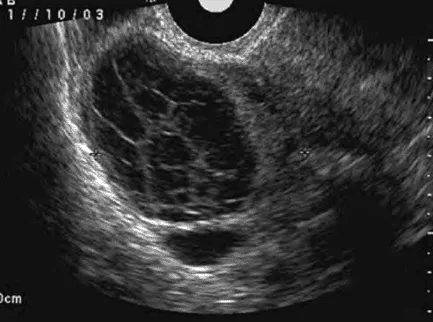

Phần tiêu đề “Nang hoàng thể”Hình ảnh “Hoàng thể xuất huyết trên siêu âm”.

Hoàng thể xuất huyết:

- Khi hình thành hoàng thể, mạch máu xâm nhập lòng nang, xuất huyết thường tự cầm. Nếu xuất huyết không giới hạn, hoàng thể to > 3 cm.

- Nếu vỡ nang, có thể chảy máu ổ bụng, cần phẫu thuật cầm máu. Nếu chỉ căng nang, gây đau, xử trí giảm đau và theo dõi.